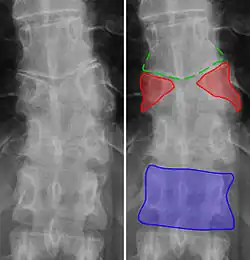

Butterfly vertebrae have a sagittal cleft through the body of the vertebrae and a funnel shape at the ends. This gives the appearance of a butterfly on an x-ray. It is caused by persistence of the notochord (which usually only remains as the center of the intervertebral disc) during vertebrae formation. There are usually no symptoms. There are also coronal clefts mainly in skeletal dysplasias such as chondrodysplasia punctata. In dogs, butterfly vertebrae occur most often in Bulldogs, Pugs, and Boston Terriers.[10]